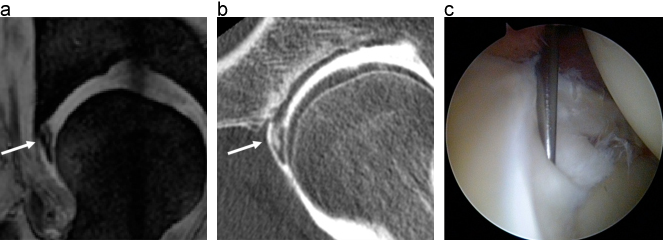

股関節唇損傷の画像診断

a、b:放射状MRIや関節造影後CTの放射状再構成像では、関節唇断裂部に信号変化や造影剤の流入がみられる(矢印)。

出典

img

1: 西井孝先生ご提供